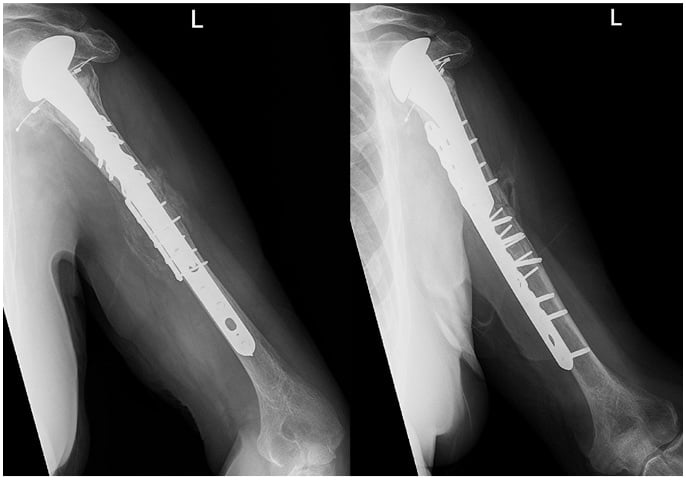

After surgery the patient was neurovascularly intact. Physical therapy included coffee-cup weightbearing with pendulum exercises for the shoulder and active and passive range of motion of the elbow, forearm, wrist, and hand. At 6 weeks postoperatively, radiographs revealed callus formation with no evidence of hardware failure (Fig. 3). The patient progressed to be weight bearing as tolerated and began active and passive range of motion of the shoulder. At final follow-up, he was able to live and function independently.

Figure 3: Radiographs at 6 weeks after surgery show callus formation.